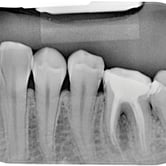

Lesión Endo-Perio Combinada

Una lesión endo-perio combinada es una condición en la que hay tanto una infección de la pulpa como una enfermedad periodontal.

Los pacientes pueden experimentar dolor, hinchazón y movilidad dental.

El tratamiento incluye tanto el tratamiento de conducto como el tratamiento periodontal para abordar ambas infecciones. La coordinación entre el endodoncista y el periodoncista es esencial.